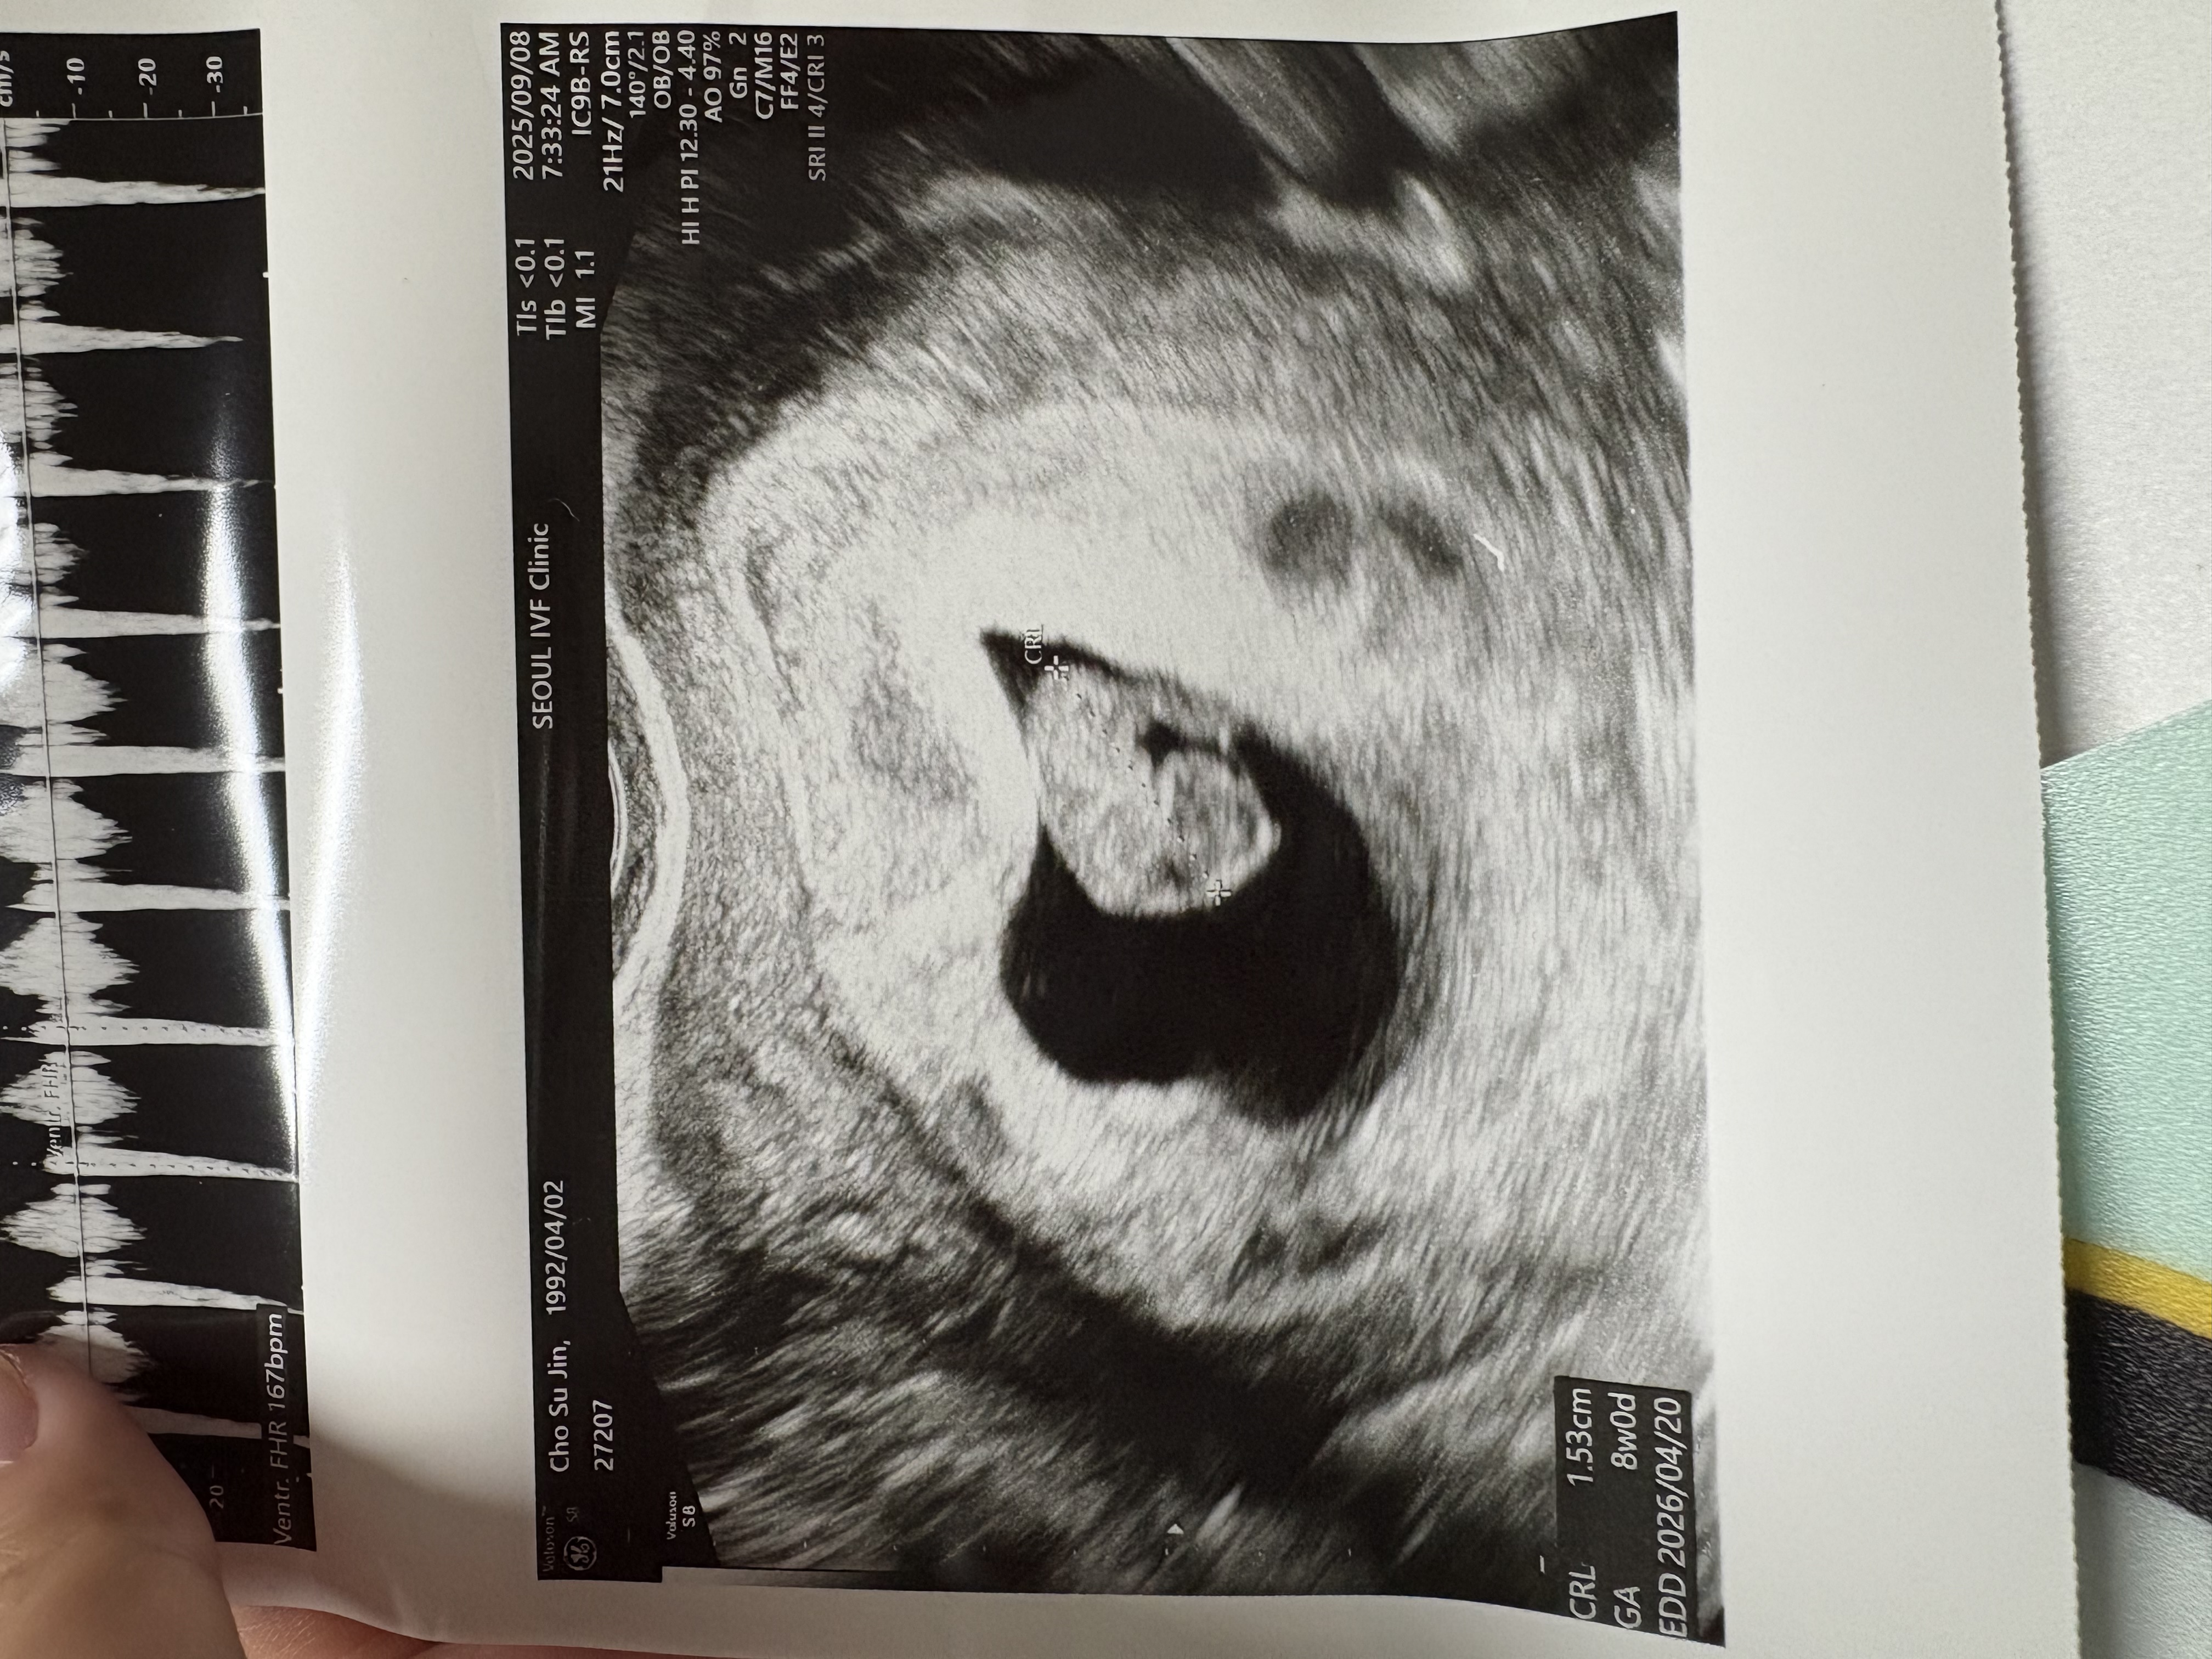

가슴 떨리는 임신 이야기를 공유해 주세요. | 임신은 새로운 생명이 자라나는 기적이에요. 처음 임신 사실을 알았을 때의 설렘, 초음파 속 아기 심장 소리에 가슴이 뛸 때, 작은 움직임을 느낄 때 모두 가슴 떨리는 순간이죠. 이 과정은 사랑과 희망으로 가득한 특별한 경험이에요. |

치료 도중 느꼈던 가장 기뻤던 순간과 절망적인 것들은 무엇인가요? 잊지 못할 경험이 있나요? | 이식 후 처음으로 임신 테스트기에서 두 줄을 확인했을 때, 그 순간은 정말 말로 다 표현할 수 없을 만큼 기쁘고 행복했어요. 마치 오랜 시간 기다려온 선물을 드디어 받은 듯한 느낌이었죠. 눈물이 날 정도로 벅차고 감격스러웠던 순간이라 지금도 잊을 수가 없어요. 하지만 그 기쁨은 오래가지 못했어요. 퇴근길에 갑작스럽게 하혈을 하게 되었고, 결국 유산이라는 너무나도 가슴 아픈 현실을 마주하게 됐습니다. 하늘이 무너지는 것 같았고, 마음 깊이 절망감에 빠졌던 기억이 아직도 생생해요. 잠깐이었지만, 그 아이가 제게 와줬다는 것만으로도 참 소중한 기억으로 남아 있습니다. |